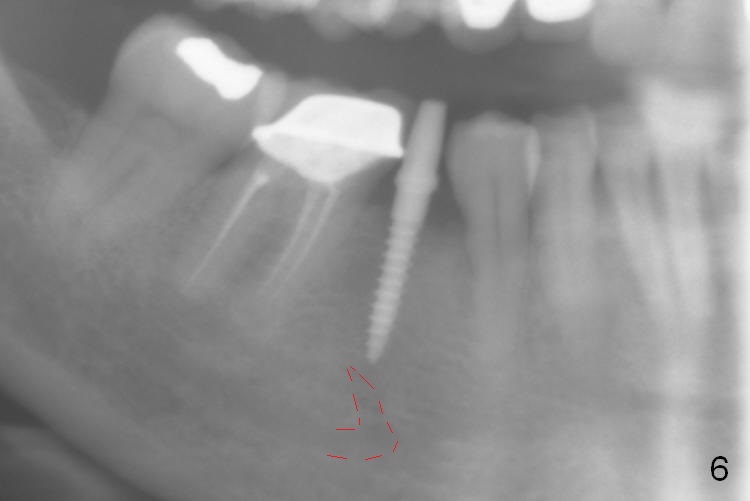

Preop photo shows the distal inclination of the tooth #28 (Fig.1). The distal surface of the latter is reduced before incision for implant placement at #29 (Fig.2). The buccolingual width is approximately 4 mm, as compared to 3 mm implant positioner (Fig.3). After 1.2x10 mm osteotomy (Fig.5), the mesiodistal cortical bone is removed with a small high-speed fissural bur (Fig.4). When a 2.5x12(2) mm 1-piece implant is placed (Fig.6), there is no buccal (Fig.7) or lingual plate perforation. There is no postop paresthesia. There is mild bone loss distal 4 months postop (Fig.8 *). Take photos before and after permanent crown cementation to show increase in ridge width after bone graft and improvement in gingival health after provisional modification. Take PA and/or BW post cementation to show that the distal bone resorption (Fig.8 *) is partially due to angulation. No continuous bone loss 15 months post cementation (Fig.9). There is mild bone resorption mesially 2 years 3 months post cementation (Fig.10). The soft and hard tissues remain healthy 4 years 3 months post cementation (Fig.11,12).